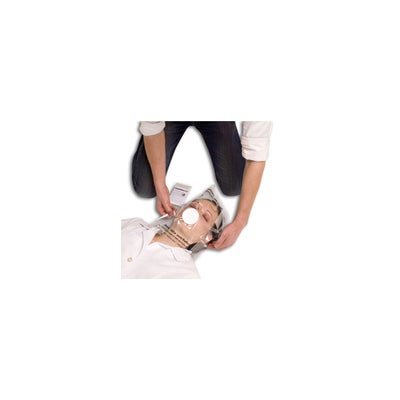

Söhngen | Beatmungstuch

- Geeignet für Mund-zu-Mund- und Mund -zu-Nase-Beatmung

- Der Filter, durch den der Patient beatmet wird, ist in eine transparente PE-Folie eingeschweisst, wodurch das gesamte Gesichtsfeld beobachtet werden kann

- Der Beatmungsfilter ist feinporig und auf beiden Seiten gegen Eindringen von Feuchtigkeit geschützt